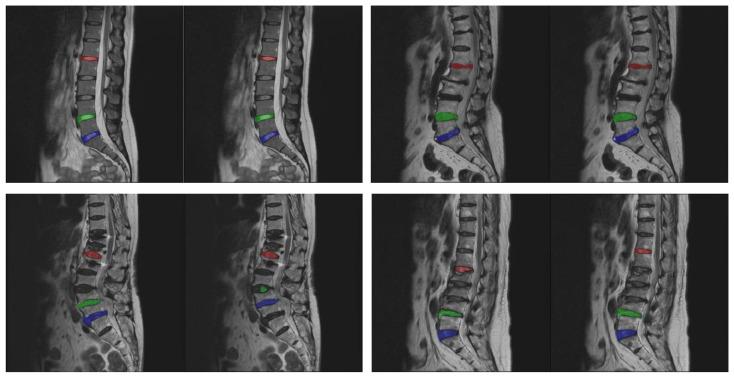

Automatically segmenting specific tissues or structures from medical images is a straightforward task for deep learning models. However, identifying a few specific objects from a group of similar targets can be a challenging task. This study focuses on the segmentation of certain specific intervertebral discs from lateral spine images acquired from an MRI scanner. In this research, an approach is proposed that utilizes MultiResUNet models and employs saliency maps for target intervertebral disc segmentation. First, a sub-image cropping method is used to separate the target discs. This method uses MultiResUNet to predict the saliency maps of target discs and crop sub-images for easier segmentation. Then, MultiResUNet is used to segment the target discs in these sub-images. The distance maps of the segmented discs are then calculated and combined with their original image for data augmentation to predict the remaining target discs. The training set and test set use 2674 and 308 MRI images, respectively. Experimental results demonstrate that the proposed method significantly enhances segmentation accuracy to about 98%. The performance of this approach highlights its effectiveness in segmenting specific intervertebral discs from closely similar discs.

对于深度学习模型来说,从医学图像中自动分割特定组织或结构是一项简单的任务。然而,从一组相似目标中识别出几个特定对象可能是一项具有挑战性的任务。本研究聚焦于从MRI扫描仪获取的脊柱侧位图像中分割某些特定的椎间盘。在这项研究中,提出了一种利用MultiResUNet模型并采用显著性图进行目标椎间盘分割的方法。首先,使用子图像裁剪方法来分离目标椎间盘。该方法使用MultiResUNet预测目标椎间盘的显著性图并裁剪子图像以便于分割。然后,使用MultiResUNet对这些子图像中的目标椎间盘进行分割。接着计算分割后椎间盘的距离图,并将其与原始图像相结合进行数据增强,以预测其余的目标椎间盘。训练集和测试集分别使用2674张和308张MRI图像。实验结果表明,所提出的方法显著提高了分割准确率,达到了约98%。该方法的性能突出了其在从非常相似的椎间盘中分割特定椎间盘方面的有效性。